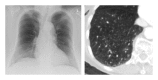

Even in a global perspective, societies are getting older. We think that diagnostic lung imaging of older patients requires special knowledge. Imaging strategies have to be adjusted to the needs of frail patients, for example, immobility, impossibility for long breath holds, renal insufficiency, or poor peripheral venous access. Beside conventional radiography, modern multislice computed tomography is the method of choice in lung imaging. It is especially important to separate the process of ageing from the disease itself. Pathologies with a special relevance for the elderly patient are discussed in detail: pneumonia, aspiration pneumonia, congestive heart failure, chronic obstructive pulmonary disease, the problem of overlapping heart failure and chronic obstructive pulmonary disease, pulmonary drug toxicity, incidental pulmonary embolism pulmonary nodules, and thoracic trauma.